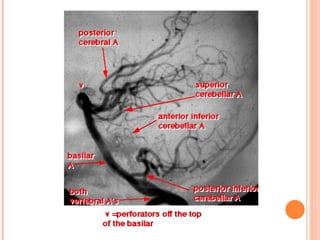

POSTERIOR CEREBRAL

ARTERY

BRANCHES

    Central branches supply

2.   Midbrain

3.   Pineal gland

4.   Lateral geniculate body

5.   Lentiform nucleus [partly]

6.   Thalamus [partly]

 Temporal branches→ inferolateral and medial

surfaces of temporal lobe, much of

parahippocampal gyrus

 Calcarine and parieto-occipital branches→

peripheral strip on lateral surface

 Calcarine branch supplies all of primary

visual cortex and some of Visual association

cortex

BRANCHES  Central branches supply 2. Midbrain 3. Pineal gland 4. Lateral geniculate body 5. Lentiform nucleus [partly] 6. Thalamus [partly]

 Temporal branches→inferolateral and medial surfaces of temporal lobe, much of parahippocampal gyrus  Calcarine and parieto-occipital branches→ peripheral strip on lateral surface  Calcarine branch supplies all of primary visual cortex and some of Visual association cortex